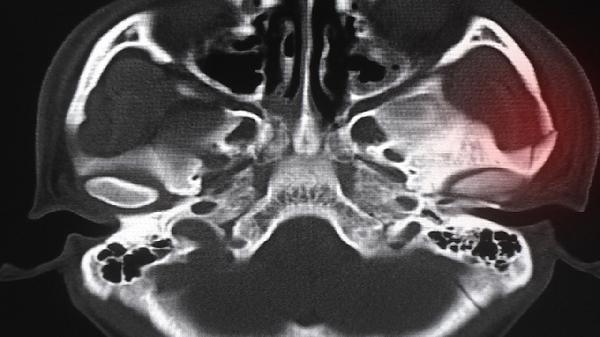

骨龄17岁对应男性青春期后期或女性接近成年,此时骨骺线可能未完全闭合。男性在骨龄16-18岁、女性在骨龄14-16岁期间通常仍存在1-3厘米的年生长空间。通过X线检查若显示长骨干骺端存在透亮带,提示软骨细胞仍有增殖能力。此时保证每日500毫升牛奶或等量乳制品摄入,配合适量跳跃类运动如跳绳,有助于刺激生长板软骨细胞分化。睡眠时长建议维持在7-9小时,深度睡眠期生长激素分泌量可达清醒状态3倍。

当骨龄片显示骨骺线完全闭合时,长骨纵向生长将终止。部分个体因青春期启动延迟,骨龄17岁时可能仍有较明显生长潜力。特发性矮小症患者即使骨龄滞后,年生长速度也可能不足4厘米。需警惕甲状腺功能减退等内分泌疾病导致的骨龄延迟假象,这类情况需先治疗原发病。